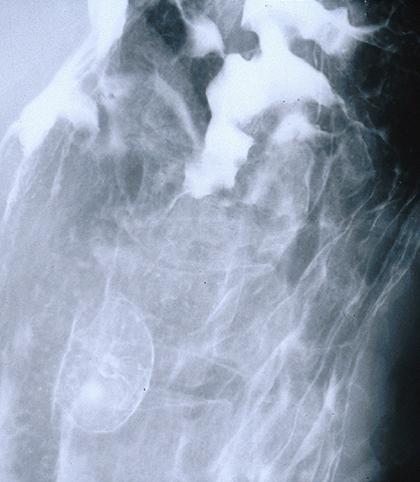

Criteria of Hist.ClassificationMalignant Lymphoma/MLP type

LocationStomach/Body

Technique, MethodX-ray

Size30 - 34